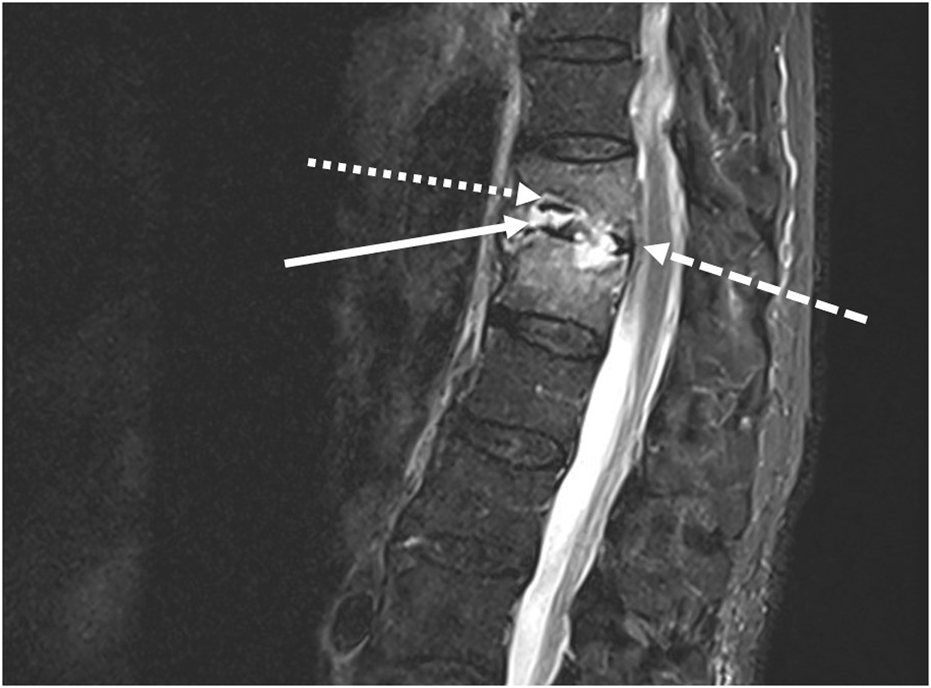

In November 2022, a 77-year-old man, weighing 78 kg, was admitted to a French tertiary hospital for opiate-resistant back pain. He had a medical history of hypertension, Parkinson’s disease and atrial fibrillation. Two months prior, he had also been treated with ofloxacin for 21 days, for prostatitis caused by extended spectrum beta-lactamase (ESBL) producing-E. cloacae. On admission to the emergency room, a neutrophil count of 8.3 G/L (N = 1.5–7 G/L) and C reactive protein (CRP) level at 87.5 mg/L (N < 0.5 mg/L) prompted the physicians to perform a lumbar magnetic resonance imaging (MRI). A T11-T12 vertebral osteomyelitis with a significant infiltration of the surrounding soft tissues and an epiduritis was found (Figure 1). The patient was admitted to the infectious disease department and a couple of days later, ertapenem 1 g q12 h was started when blood cultures flagged positive for Gram-negative bacilli. An ESBL-producing-E. cloacae (Table 1) was identified. After 8 days of ertapenem therapy, the patient still had fever and CRP level remained at a plateau of 70 mg/L. Blood cultures drawn at this point were positive for carbapenem-resistant E. cloacae (Table 1). No carbapenemase enzyme was found (Xpert® Carba-R test, Cepheid, CA, United States and β CARBA test) and resistance to ertapenem was explained by a combination of impermeability with ESBL and AmpC-beta-lactamase. Extended-infusion meropenem 2 g q8h over 3 h was started according to the 2022 Infectious Diseases Society of America (IDSA) guidelines (Tamma et al., 2022) for infections caused by non-carbapenemase producing carbapenem-resistant Enterobacterales (non-CP-CRE) resistant to ertapenem, that remain susceptible to meropenem (Table 1). On the first day of treatment, a single dose of amikacin (30 mg/kg) was also administered. Blood cultures were negative after 5 days of treatment. However, back pain and fever persisted, the patient became disoriented, and CRP level rose to 99 mg/L. Clinical failure and drug neurotoxicity related to the use of a high dose of meropenem despite reduced renal clearance (estimated glomerular filtration rate, eGFR, at around 40 mL/min/1.73 m2 at this point) were suspected. Therefore, we decided to change the antibiotic therapy.

FIGURE 1

Medullar magnetic resonance imaging: Decreased height and STIR hypersignal of disc (white arrow) with irregularity and erosion of T11-T12 vertebral body endplates (white dotted arrow), and epidural collections (white dashed arrow).